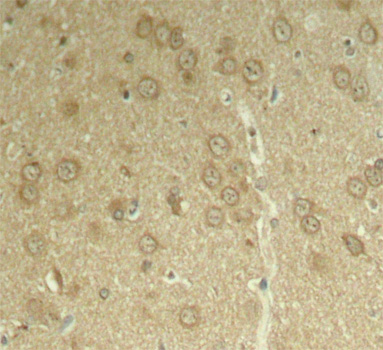

• AP0168: image 2

Immunohistochemical analysis of paraffin-embedded rat hippocampal region tissue from a model with Alzheimer, using phospho-MAPT-T205 antibody.